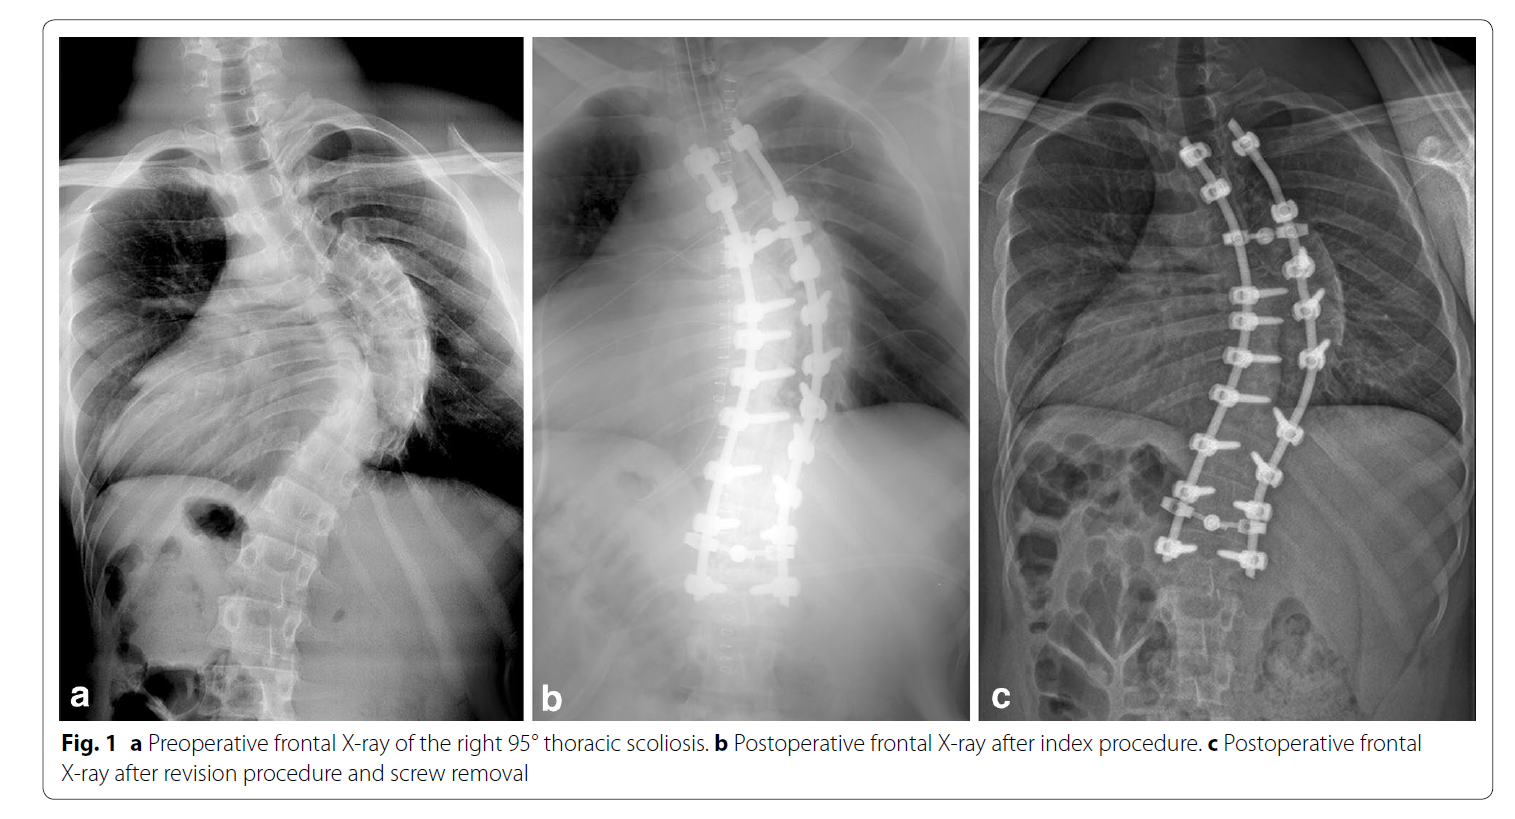

病例报告。19岁男性,脊柱侧凸手术,T2-L1固定,置钉过程SEP正常,矫形上第二根棒时波幅下降90%,唤醒下肢不能活动。减少矫形度数后波幅没有完全恢复,术后病人没有神经症状。6月后病人逐渐出现痉挛性瘫痪表现,下肢肌力4级,肌张力增高,病理征阳性。CT和MRI显示左侧T5椎弓根钉进入椎管。翻修手术取出左侧T5钉子,3月后脊髓症状消失。